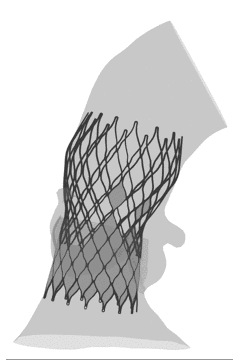

FEops评估瓣膜释放稳定性

根据FEops评估报告,起始释放位置与最终稳定位置具有一定的差异,评判瓣膜移位风险较大,建议使用VenusA-Plus确保患者手术安全。

L26号瓣膜标准位植入后的稳定形态